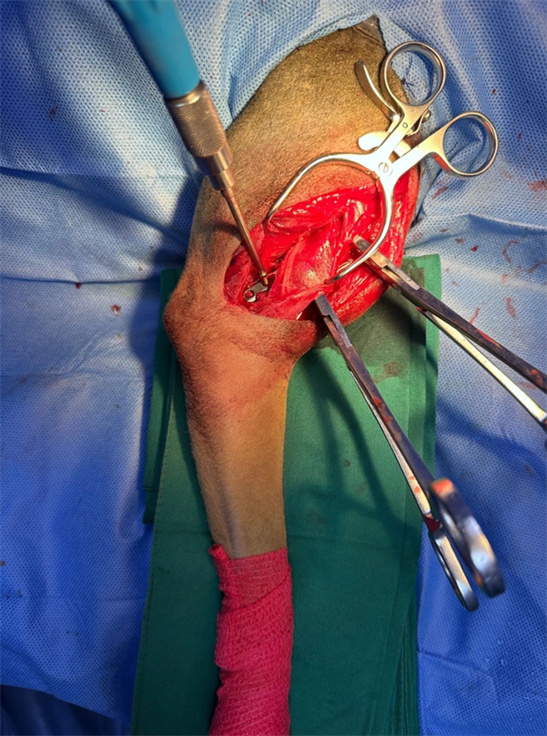

The lateral approach is used for the transverse fracture of the right humeral shaft, with full open contact for fixation of the head side and lateral dual Bone Plates. The transverse fracture plate hole is reduced with compression screws on the head side bone plate.

As it is a PRCL locking bone plate system, strive for perfect bone plate shaping, but do not deliberately pursue absolute shaping perfection